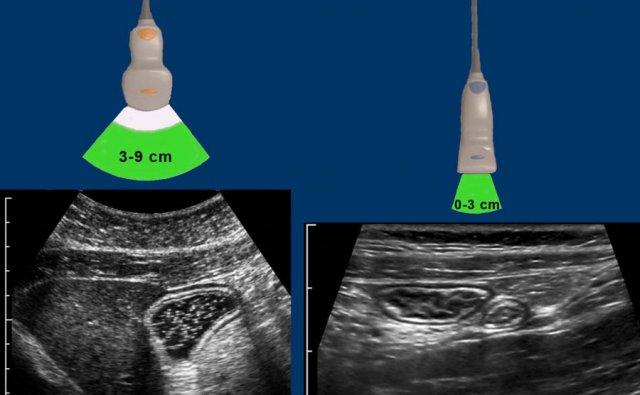

Ở người gầy này, hồi tràng tận bình thường và ruột thừa bình thường đang bị ép xẹp (mũi tên) được hiển thị trên máy tính bảng kết nối với đầu dò trị giá 1.200 euro.

Đối với chương trình siêu âm bụng thông thường với bệnh nhân có thể trạng khác nhau, tối thiểu cần có ba đầu dò.

Các con số cm biểu thị khoảng độ sâu mà tại đó độ phân giải hình ảnh đạt mức tối ưu.

Do ruột nằm gần thành bụng, đầu dò cỡ trung và cỡ nhỏ là những đầu dò chủ lực trong siêu âm đường tiêu hóa.

Việc lựa chọn đầu dò dựa trên độ sâu mà ruột được hiển thị trong quá trình ép.

Ví dụ, dạ dày chứa đầy dịch ở bệnh nhân béo phì (bên trái) được khảo sát tốt nhất bằng đầu dò cỡ trung, trong khi hồi tràng và ruột thừa bình thường ở bệnh nhân gầy (bên phải) được khảo sát bằng đầu dò cỡ nhỏ.